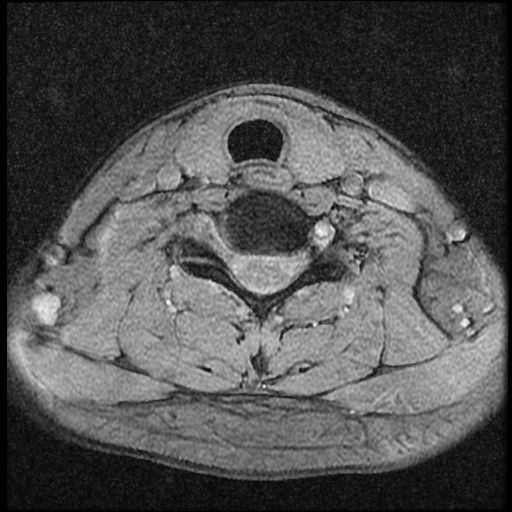

근대 21년 사고 이후부터 목쪽이 계속 아픈 상태 여서 사고로 인한 급성인지 우연이 겹친 민성 디스크 인지 확인하고 싶습니다~

이 MRI 사진은 21년도 사고 당시 찍은 MRI 사진 입니다. 확인 부탁드립니다~

전체 mri를 다 봐여겠지만 보여주신 mri 컷에서는 의미있는 경추 디스크탈출이 보이지 않습니다.